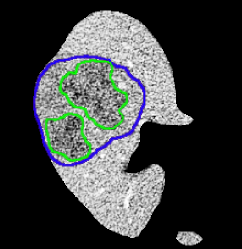

Experimental Results. Since we do not have the ground truth for the LiTS test set, we first perform the two-fold cross-validation on the training set to quantitatively and qualitatively evaluate the performance of our proposed method. We obtain Dice per case and some visual samples are presented in Fig. 6.

Observations on LiTS Annotations. As shown in Fig. 6, the LiTS annotations have both over-segmentation and under-segmentation issues. For the large lesions in both cases shown in Fig. 6, our predictions better fit lesions compared to the ground truth; while for the small lesions, our predictions locate more lesions potentially missing in the ground truth. Similar observations have been reported in [4]. Due to the imperfect ground truth provided by the LiTS challenge, we argue that the metrics computed against the ground truth probably could not be the only way to compare the segmentation results. Visual results could be considered as well and ours indicate the efficiency of our method.